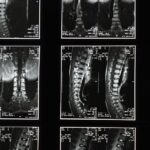

La décompression spinale fait référence à une technique thérapeutique qui cherche à réduire la pression sur les disques intervertébraux. Cela est crucial pour les personnes souffrant de conditions telles que la hernie discale, le bombement discal ou la sténose spinale. À travers une traction douce et contrôlée, cette méthode facilite l’amélioration de la circulation sanguine et la régénération des tissus.

La décompression spinale est un traitement non-invasif conçu pour réduire la compression exercée sur les structures vertébrales. Cette thérapie agit en effectuant une traction douce et contrôlée qui permet de soulager la pression sur les disques intervertébraux. Cela favorise non seulement la circulation sanguine, mais contribue également à la régénération des tissus, apportant ainsi un soulagement significatif des douleurs dorsales.

Cette technique consiste à appliquer une traction douce et contrôlée sur la colonne vertébrale afin de réduire la pression exercée sur les disques intervertébraux. En décompressant ces disques, on facilite une meilleure circulation sanguine et on favorise ainsi la régénération tissulaire. Ce processus permet non seulement de soulager les douleurs, mais également de contribuer à la guérison de l’ensemble du dos. La décompression spinale est idéale pour les patients qui cherchent à éviter des interventions chirurgicales invasives et qui souhaitent s’orienter vers des méthodes plus douces.